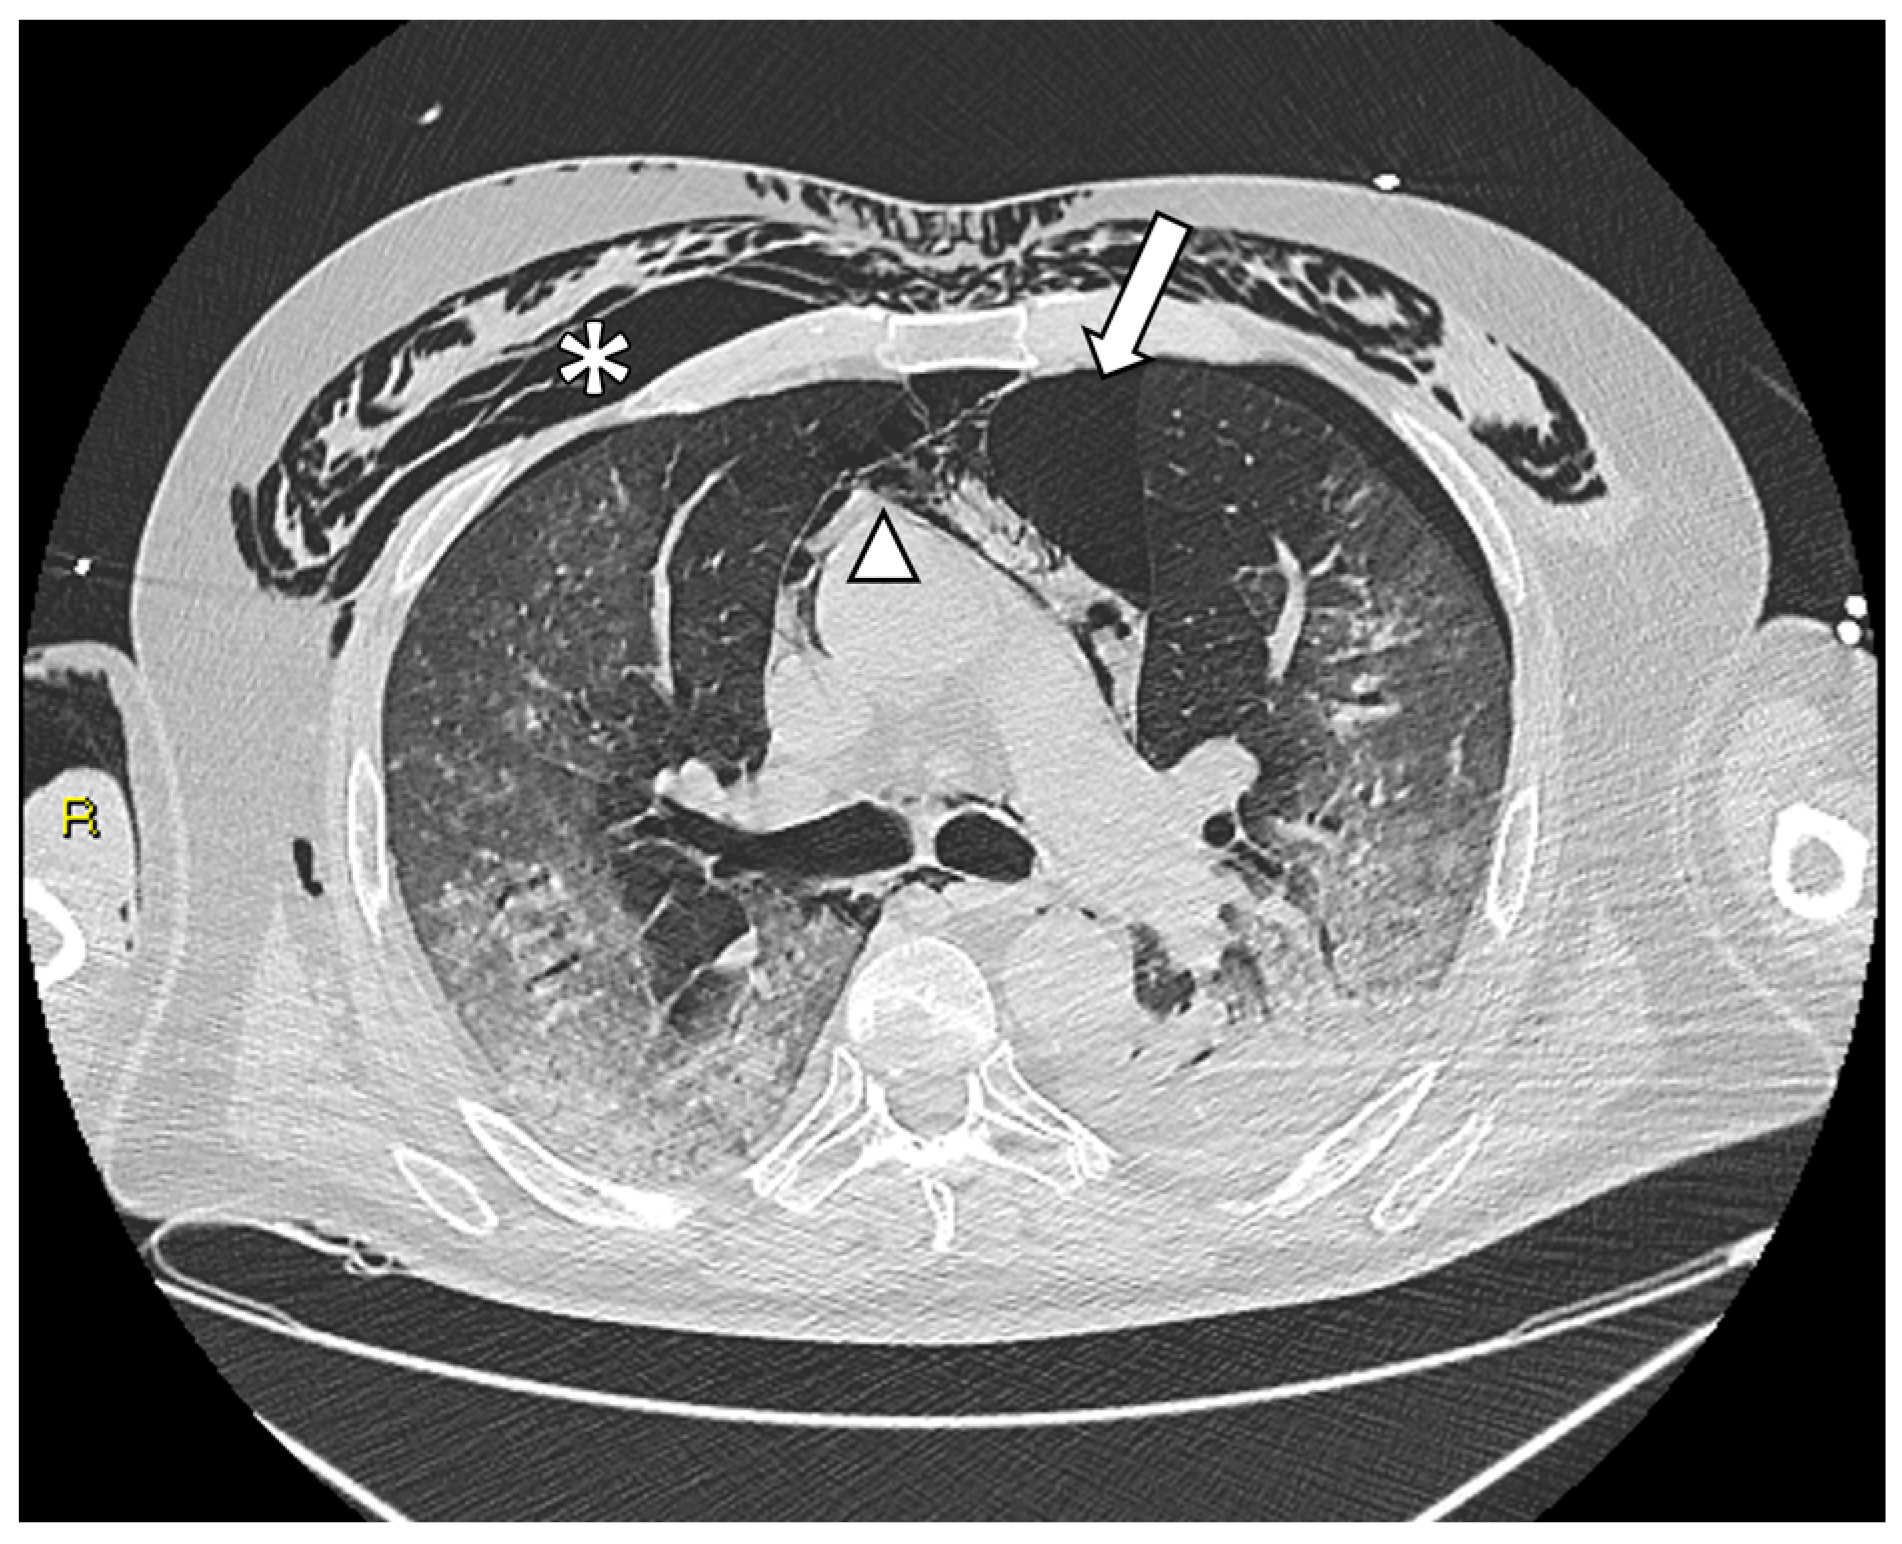

2.3. Imaging Acquisition and Analysis—CXR and CT